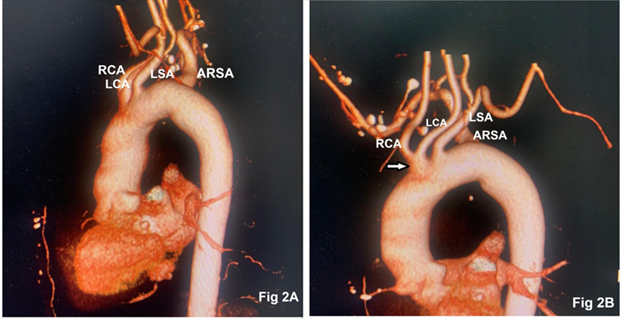

We present a case series involving two adult patients scheduled for elective cardiac surgery who were found to have ARSA. Detailed patient information is summarized in Table 1. Computed tomography (CT) of the chest confirmed the ARSA originating from the posteromedial part of the arch of the aorta distal to the origin of the left subclavian artery and coursing posterior to the esophagus in both patients (Fig 1). The retroesophageal course of the ARSA did not exhibit any compression of the esophagus or trachea. Both patients had a left-sided aortic arch along with a common origin of the right and left common carotid artery (Fig 2). The intraoperative course, including the placement of invasive monitoring lines, cannulation, and the conduct of cardiopulmonary bypass, proceeded as planned without complications. The anticipated surgical procedures and postoperative recovery were unremarkable.

Figure 2: Digital reconstruction of axial computed tomography depicting RCA (right carotid artery), LCA (left carotid artery), LSA (left subclavian artery), and ARSA (aberrant right subclavian artery, Fig 2A). Combined origin of RCA and LCA (arrow) from the aortic arch (Fig 2B)